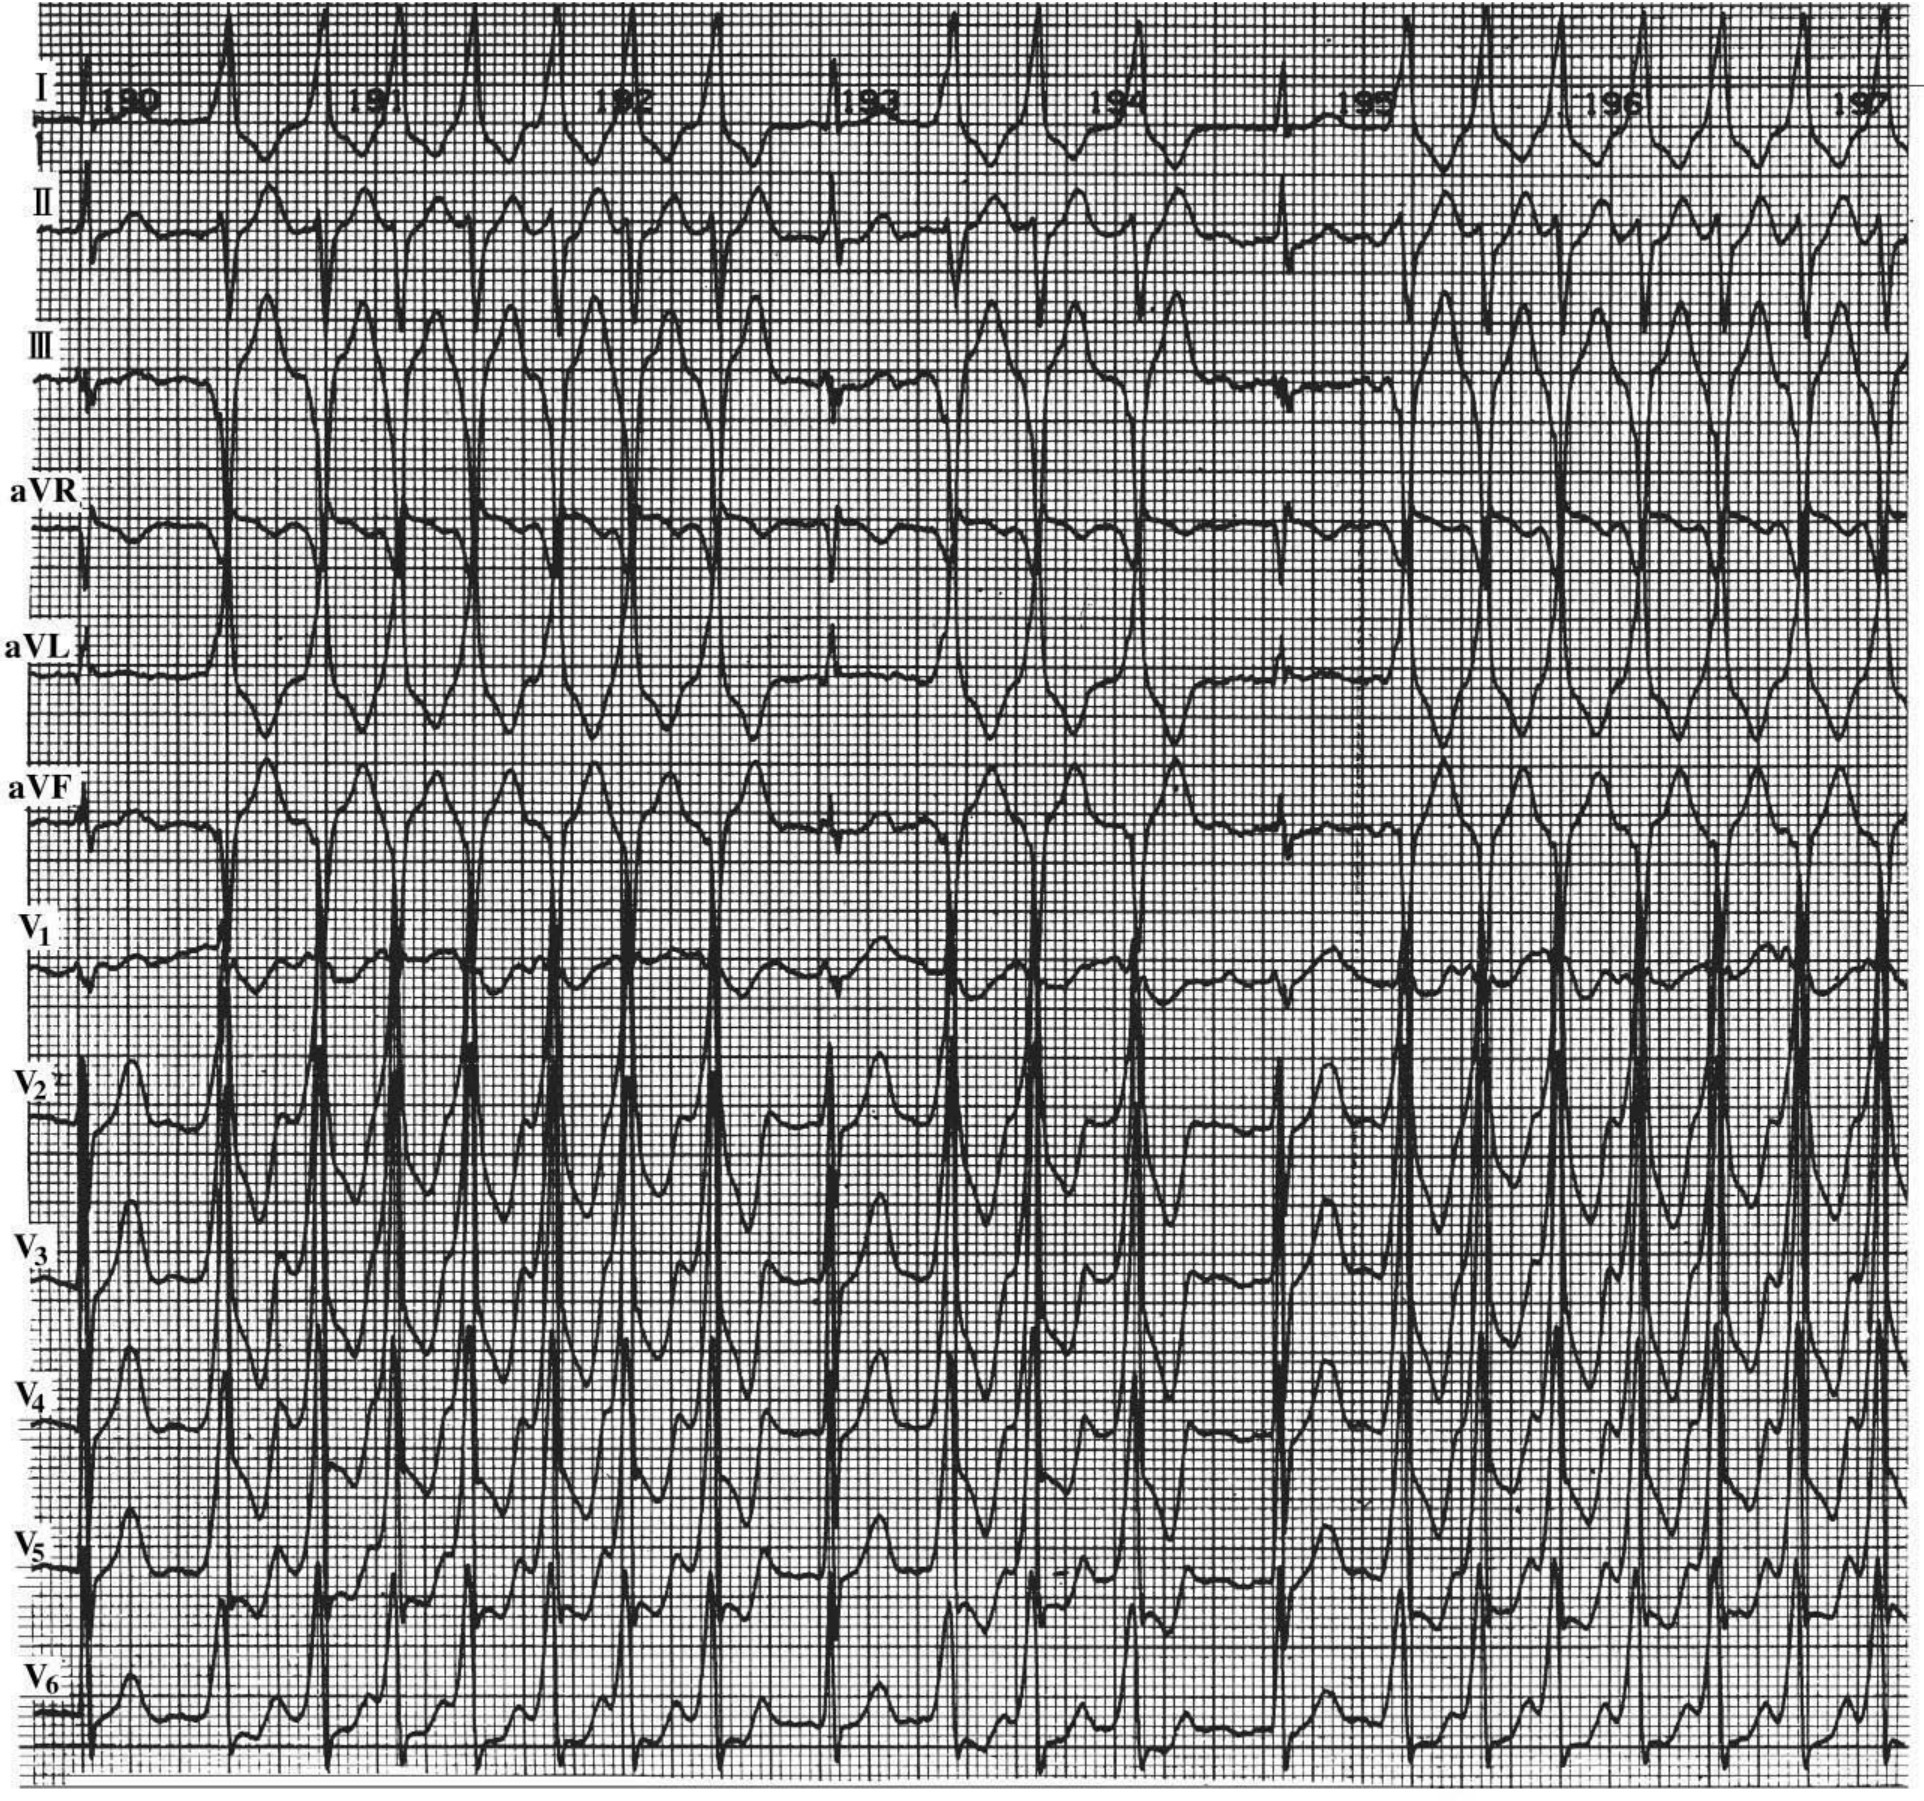

2.快速型心房颤动 心室率100~180次/min,新近发生的未经治疗的心房颤动多属此型,是常见而典型的心房颤动(图34-11)。可见于各种病因所致的心房颤动。

图34-11 心房颤动伴时相性室内差异性传导

男性,56岁,高血压病,心律失常。P波消失,代之以f波,R-R间期绝对不等,平均心室率178次/min。Ⅱ导联R3~R6连续出现宽大畸形,呈右束支传导阻滞图形,异常QRS波形态随心室率快慢变化表现出一定的变化,形态恢复正常时无类代偿间歇。R9为单发的室内差传。结论:快速型心房颤动房颤伴连续性室内差传